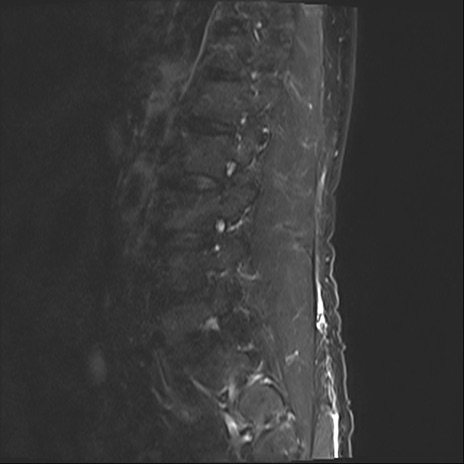

【整形】TIPS症例2 腰椎MRI STIR(矢状断像)

【症例】70歳代男性

【主訴】左下肢痛

【現病歴】2週間前くらいから腰痛、左下肢痛あり。左臀部から大腿、下腿外側のしびれが常時ある。歩行とともに同部位の痛みあり。

【身体所見】Lasegue70-/60+、Bragard-/±、PTR ±/±、ATR -/-、IP 5/5、TA 5/4、TS 5/5、EHL 右第1足趾なし/3、FHL 5/5、hypersthesia(-)、足背動脈触知良好

異常所見と診断は?